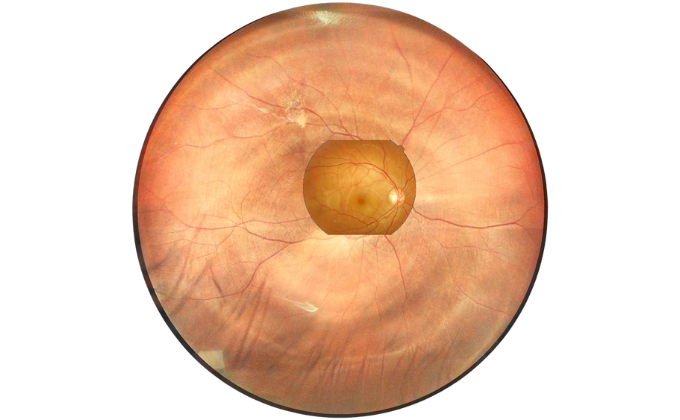

Retina Examination Under Cataracts

Examining fundus diseases through cataracts is a crucial topic in ophthalmology. Traditional fundus cameras cannot see through cataracts to capture fundus conditions. However, our DF600 scanning laser ophthalmoscope can penetrate moderate cataracts, providing a glimpse into the fundus and offering greater convenience for fundus examinations in patients with cataracts.

Ultra Wide Field of View

An 80-degree optical fundus image and a 130-degree laser fundus image, a more intuitive comparison, help you choose the fundus camera that suits you best.

Compared to 60-degree optical fundus images, our 168-degree laser fundus camera shows more dimensions and details, helping you make a more accurate diagnosis.